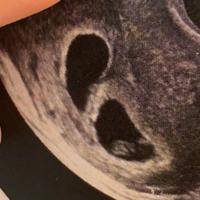

问题描述:今年30岁,之前生育过一个孩子,试管生的,如今再要个二胎,经过我和老公经过长时间努力,终于又成功了,要去做一超了,想问问要看什么数值才能判断胎儿正常的发育?最佳回答:试管婴儿移植后的一超检查通常在移植后28-30天进行,主要通过观察孕囊、卵黄囊、胎芽和胎心等指标来判断胎儿是否正常发育。如果这些指标均正常,说明胚胎在宫内发育良好,妊娠情况较为稳定。如果有任何异常,建议及时与医生沟通并进行进...

问题描述:我是一名35岁的大龄女性,因为身体原因无法自然生育所以就决定去做试管治疗。目前我已经移植快一个月了,马上就要去做一超检查。之前验孕只能确定怀上了,但无法清楚看到是怀单胎还是双胎。所以想问问从一超的检查单子上就能确定具体妊娠情况吗?最佳回答:做试管一超能够确定是单胎还是双胎。试管移植后一超一般安排在移植4-6周时进行,此时孕囊发育会很明显,通过B超检查能够清晰看出妊娠情况。移植后做一超的目...